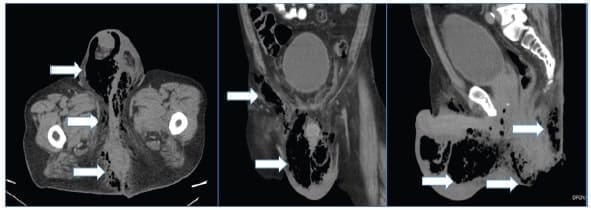

La tomografía computarizada es considerada actualmente la principal herramienta imagenológica 26; es útil cuando se sospecha compromiso de los tejidos profundos o del espacio retroperitoneal. Es específica para determinar la extensión de la enfermedad, etiología subyacente, engrosamiento de los planos faciales con presencia de gas e infiltración de la grasa (figuras 2 y 3) 32,53.

Figura 2. Tomografía computarizada que muestra el proceso inflamatorio enfisematoso que afecta la región perianal, genital, glútea e inguinal derecha. Se observa proceso enfisematoso a nivel de la grasa peri-rectal. Las flechas blancas señalan las áreas de enfisema.